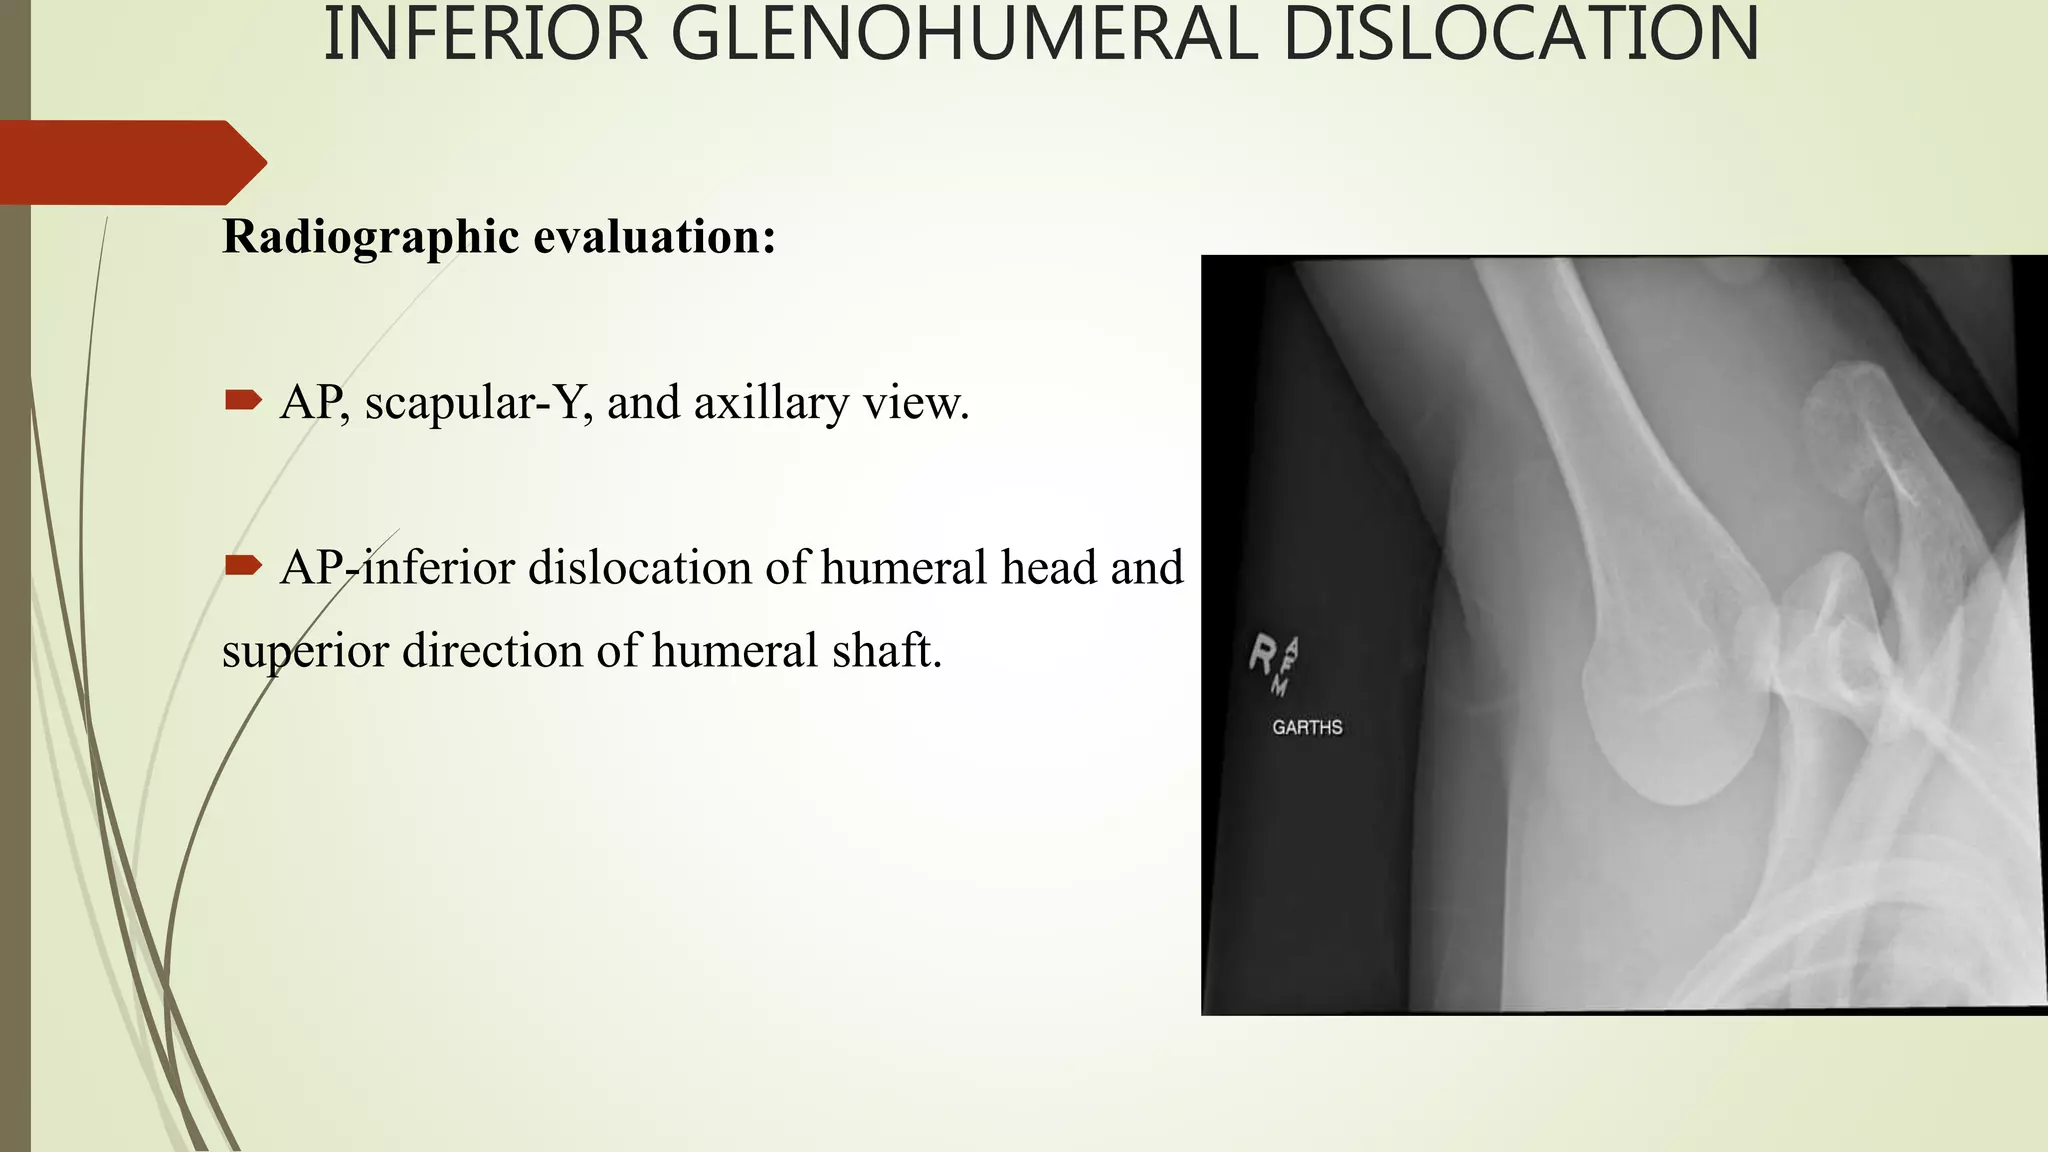

- Clinical evaluation and radiographs are used to diagnose the type of dislocation and assess for complications like fractures.